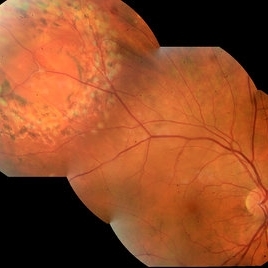

Diabetic Macular Edema Diabetic Macular EdemaFeb 12 2020 by DIEGO TOLENTINO Proliferative diabetic retinopathy plus diabetic macular edema (cystoid). Photographer: Diego Tolentino, CEOP Condition/keywords: diabetic macular edema, diabetic retinopathy